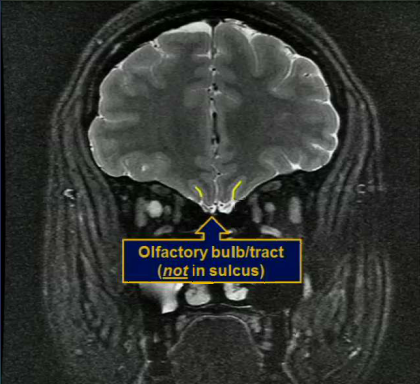

Where are olfactory bulbs and tracts located?

Not in the sulcus. It is UNDER the sulcus in the subarachnoid space.z